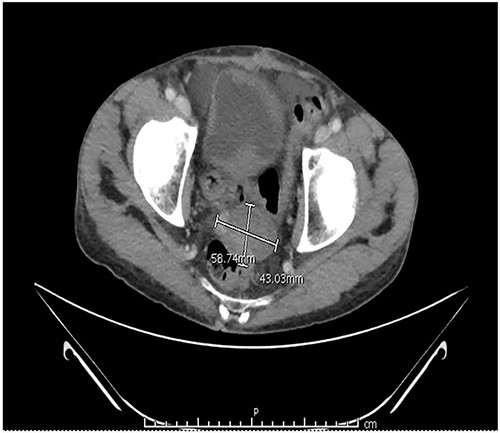

Two months after the tumor was grossly resected and 1 month into Imatinib treatment, the patient presented to the Emergency Department with complaint of abdominal discomfort, constipation and nausea. CT abdomen and pelvis noted mid small bowel distention, suggestive of partial small bowel obstruction with mild ascites. Importantly, a mass-like focus measuring 5 × 3.8 cm was found in the pelvis anterior to the rectosigmoid junction (Fig. 3). A nasogastric tube was subsequently placed and the patient was administered empiric antibiotics. Considered a failure of conservative management, the patient was taken to the operating room again for an exploratory laparotomy, lysis of adhesions and debulking of the mass. The patient tolerated the procedure well with no complications. The patient maintained a typical postoperative course and was discharged with oncological follow-up and continued Imatinib treatment. On 2 and 4 months follow-up CT, the pelvic mass measured 4.1 × 3.3 and 2.6 × 2.7 cm (Fig. 4), respectively.

CT abdomen and pelvis at (A) 2- and (B) 4 months follow-up. The pelvic mass measured 4.1 × 3.3 and 2.6 × 2.7 cm, respectively.